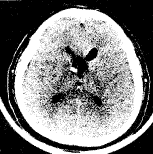

随着科学技术的发展,神经内窥镜手术的应用范围不断扩大。作为外科手术的一项新技术,神经内窥镜技术已应用到从诊断到治疗的神经外科许多领域。最近我院神经外科配置了美国Ckarus公司生产的神经内窥镜治疗系统,其中包括脑室镜、观察镜、治疗镜及与之配套的显微手术器械,我们应用该套设备行脑室-腹腔分流管的置入和脑脓肿的清除术数例,行第三脑室内蛛网膜囊肿合并脑积水和透明隔囊肿造瘘术各1例 ......